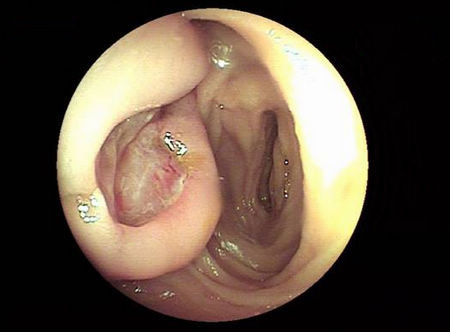

幼年性息肉

由于这种息肉的腺管呈囊性扩张,充满粘液,故亦称潴留性息肉,也是一种错构瘤性息肉,但与Peutz-Jeghers综合征不同,它没有粘膜肌层的树枝状增生。其发病在4岁及18 ~ 22岁呈现两个高峰。儿童的消化道息肉中,90%以上为幼年性息肉。

内镜下,幼年性息肉呈紫红色的球形息肉,不分叶,表面常有糜烂或附着白苔,多有蒂。幼年性息肉可自行脱落,内镜下切除后一般不会复发。